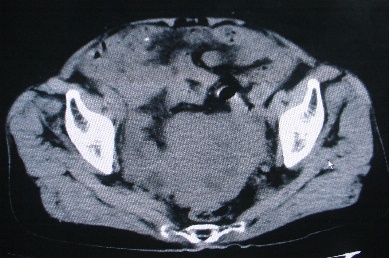

以下是引用卜一在2007-4-30 15:29:00的发言:[br]子宫明显增大,不规则,子宫壁不规则增厚,子宫腔明显缩小,子宫右侧软组织团块与子宫关系密切,内见低密度坏死区。考虑:子宫癌并周围侵润。